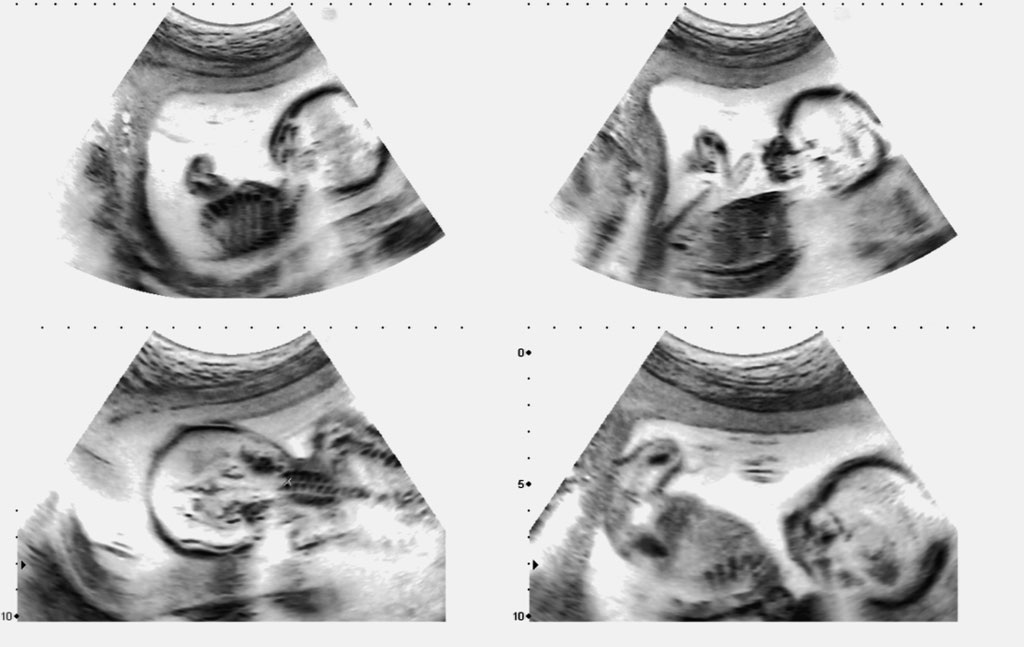

وبعيداً عن الاختراعات العسكرية، يمكن الجزم أن الإنسانية لم تستفد في أي مجال من معرفتها العلمية لطبيعة الصوت مهما اختلفت أطوال موجاته ورجع صداها، مثلما استفادت من ذلك في الطب الذي توصَّل إلى تصوير الأنسجة والأعضاء الداخلية في جسم الإنسان بفعل الصدى (Echography). وتعتمد هذه التقنية على جهاز يُسمَّى الترجام بتحويل التيار الكهربائي إلى موجات ما فوق صوتية يزيد ترددها على 20.000 هيرتز، غير مسموعة بالأذن البشرية، ويرسلها إلى أنسجة الجسم. وفي تلك المرحلة، تتم تغطية المساحة المراد تصويرها بهلام، يضمن احتكاكاً أفضل لمصدر الموجات ما فوق الصوتية بجلد الجسم لأن وجود فراغات هوائية ما بين الآلة والجلد قد يشوش حقيقة الصورة.

وعندما ترتد تلك الموجات عن المكونات الداخلية للجسم، يلتقط المحول هذه الارتدادات، ويحولها إلى إشاراتٍ كهربائية. ومن ثم يتولى جهاز الكمبيوتر تحويل الإشارات الكهربائية إلى صورة يجرِي عرضها على شاشة، أو تسجيلها على شريط فيديو أو كصورة كمبيوتر رقمية. ومن أكثر استخدامات التصوير الطبي بالموجات ما فوق الصوتية استكشاف حالة القلب والأوعية الدموية، معرفة جنس الجنين بعد الأسابيع الأولى وصحة تكوينه ونموه، إضافة إلى تشخيص حالات المرارة، المثانة، الكبد، البنكرياس وغير ذلك الكثير من أعضاء الجسم الداخلية. والواقع أن مبدأ إطلاق موجات صوتية ورصد ما يتكشف عنه صداها، كان بدوره فاتحة تطوير سلسلة من الاختراعات والابتكارات القائمة على إطلاق نبضات مغناطيسية ورصد ارتداداتها. مثل جهاز التصوير الطبي بالطنين المغناطيسي، وأجهزة كشف المعادن في باطن الأرض. وهي أجهزة بلغت مستويات فائقة من الدقة، بحيث إن بعضها بات قادراً على اكتشاف نوع المعدن في باطن الأرض قبل بذل الجهد في استخراجه. ومن أهم استخداماتها الكشف عن الألغام المدفونة في الأرض لتفكيكها. ووصلت استخدامات الصدى إلى الموسيقى. فمنذ الخمسينيات بذل موسيقيون جهوداً أثمرت في إضافة صدى معيَّن على بعض الجُمل الموسيقية لاعتبارات فنية وجمالية، وذلك باختراع جهاز “الإيكوبلكس” الذي يعيد إنتاج الصوت المسجَّل على شريط ممغنط مرة أخرى أو عدة مرات بفارق زمني قصير جداً. ومنذ بدايات القرن الحالي، شاع استعمال الدوائر الإلكترونية للحصول على مؤثر الصدى في التسجيلات الموسيقية الحديثة.